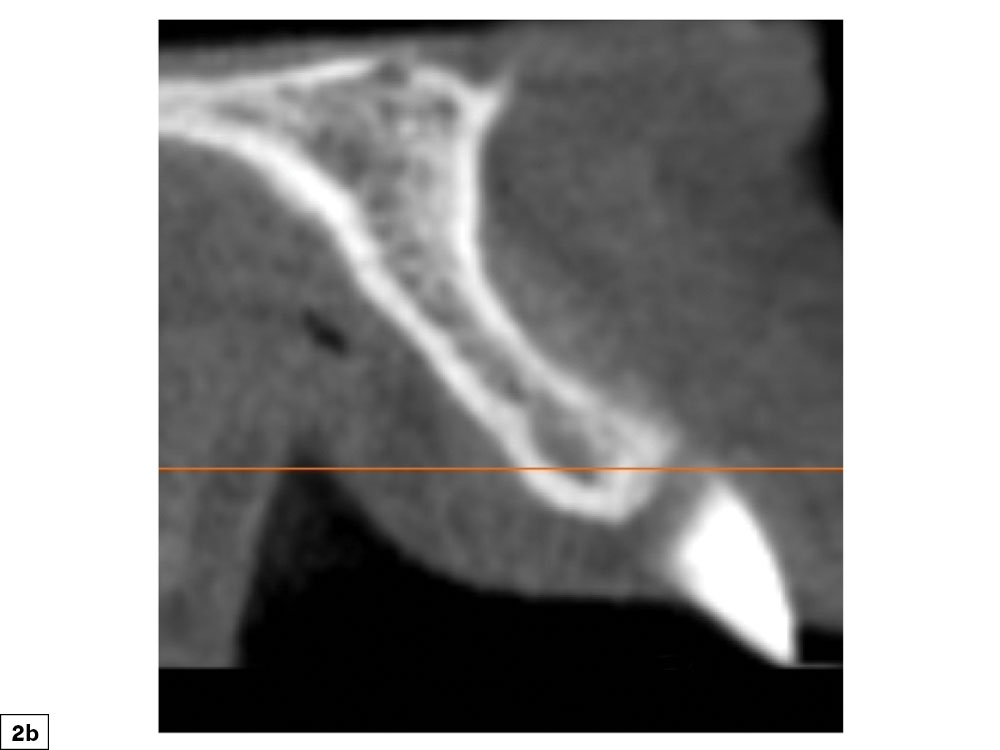

A concavity-type defect is a horizontal deficiency greater than 2 mm. These bony defects have surrounding bone that may be utilized for graft support and containment of graft material. This is advantageous for space maintenance, which allows for more predictable graft healing. These depression-type bony defects are ideal for clinicians early in their learning curve for ridge augmentation procedures, as they are highly predictable (Figs. 2a, 2b). Depending on the size and location of the deficiency, tenting screws may be required for space maintenance principles.

Figures 2a, 2b: Concavity bony defect: Concave defect, which allows for predictable bone grafting procedures.